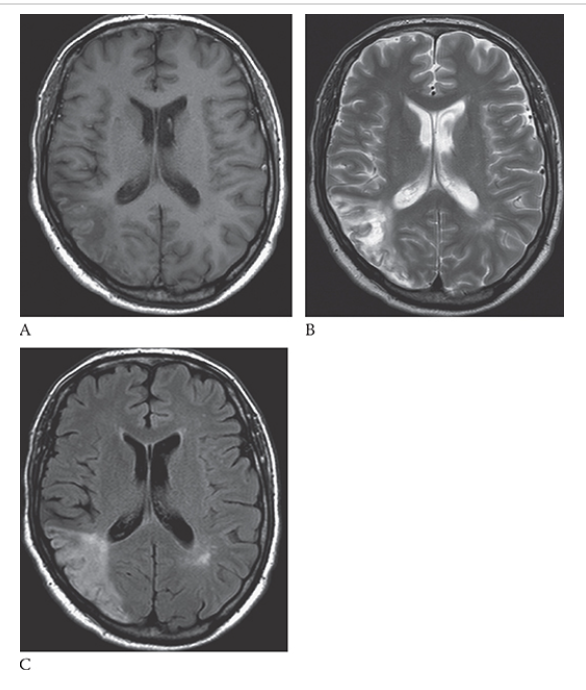

What is A

Glioblastoma Multiforme. shows an isointense mass with low-signal central necrosis and surrounding edema. Postcontrast T1W image

What is B

Glioblastoma Multiforme.hows peripheral irregular enhancement. FLAIR image

What is C

Glioblastoma Multiforme. shows high-signal edema.